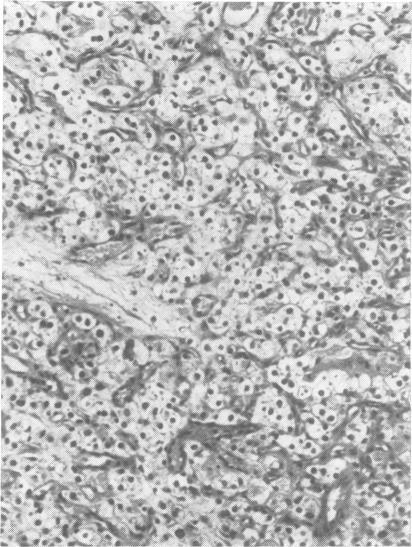

A retrospective study has been carried out on 67 patients harbouring 78 posterior fossa haemangioblastomata. The site, macroscopic nature, and histological features are described, and correlations sought with the degree of erythrocytosis in the peripheral blood. The problems of aetiology are discussed and a single hypothesis advanced.